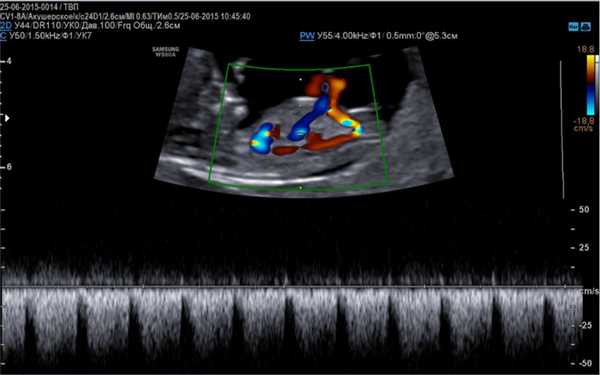

- эхо-КГ - это высокочувствительный метод, который позволяет рассчитать количество жидкости между сепарированными листками перикарда, измерить размеры сердца, оценить его насосную и сократительную способность, а также выявить возможную причину гидроперикарда (например, онкологию).

Пока - наблюдение и через 2 месяца - нужно сделать обычную стандартную эхокардиографию с цветным допплеровским картированием.

Вам нужно выполнить повторно ЭХОКГ, причем обязательно с цветной допплерографией внутрисердечных потоков крови

Основой для качественной диагностики является наличие программы, позволяющей определить функциональное состояние сердечно-сосудистой системы на приборе, оснащенным специальным датчиком, имеющим частоту сканирования не менее 5 МГц, а также цветное картирование системы кровообращения и доплер.